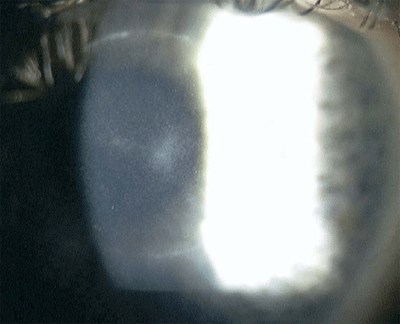

该患者由于远视进行了PRK手术,为了达到9mm的远视治疗区需要去除9.5mm的上皮。术后患者使用氧氟沙星和氟米龙每天4次点眼。术后第6天时,他的右眼角膜中央仍有1-2mm的上皮缺损,于是更换了角膜接触镜。在术后第7天时,上皮缺损愈合,但仍存留有由于几天前的上皮缺损所导致基质浸润。去除了角膜接触镜,并将氧氟沙星用量增加至清醒时每小时一次,同时加用强化的头孢唑林和红霉素眼膏每天4次。术后第8天时,上皮仍保持完整,中央浸润吸收,但在原有的中央浸润周围形成了一个新的环状浸润灶(图2)。细菌,真菌,病毒,棘阿米巴和分枝杆菌培养结果均为阴性。局部强化使用抗生素以及去除角膜接触镜对患者有效。术后一年裸眼视力为20/20,最佳矫正视力达到20/15,没有明显的角膜瘢痕。

图2 患者4为右眼远视矫正PPK术后第8天。注意角膜中央2mm的浸润及其周围环状浸润。虽然培养结果为阴性,该患者仍按感染性角膜炎进行治疗,最终的裸眼视力为20/20。